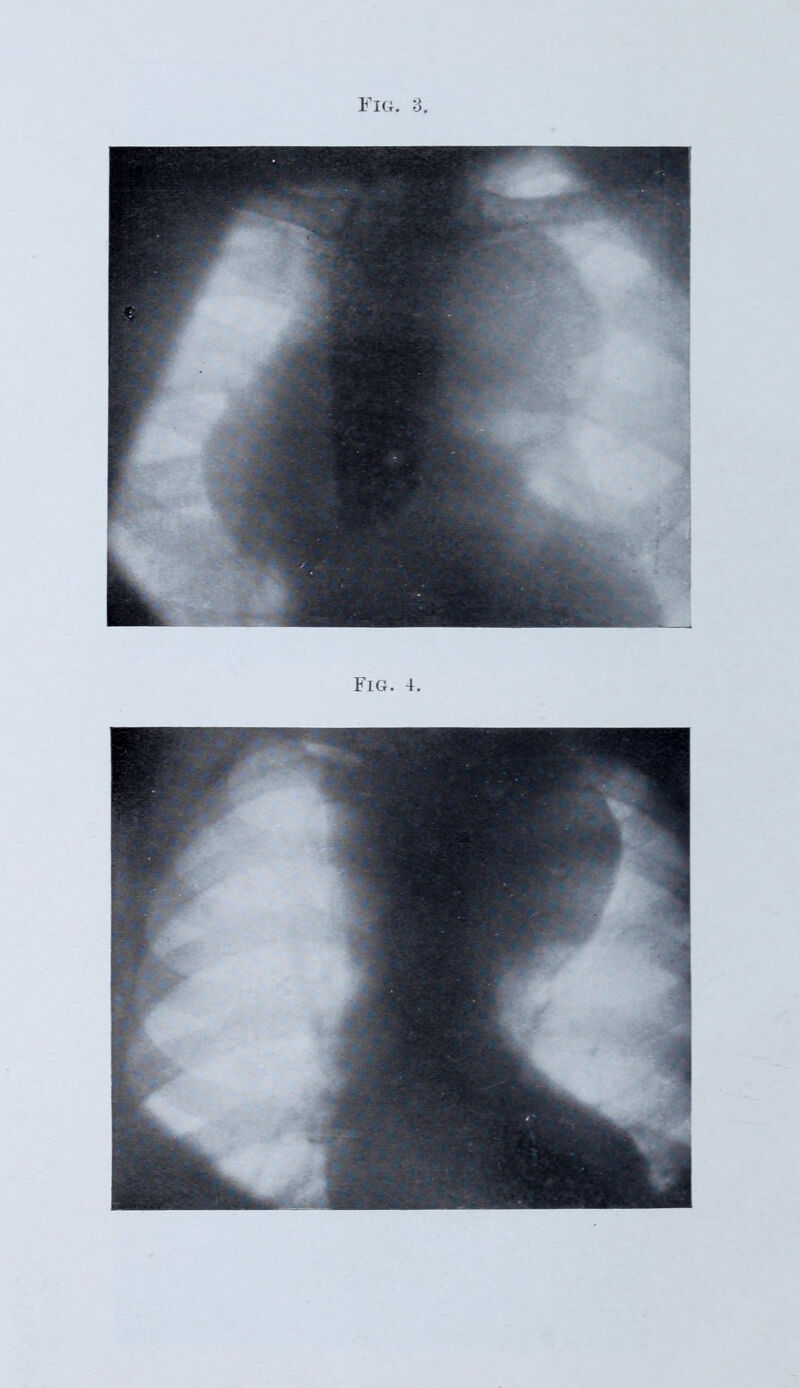

The Lumleian lectures on intrathoracic aneurysm : delivered before the Royal College of Physicians of London on March 6, 11 and 13, 1913 / by F. de Havilland Hall.

Credit: The Lumleian lectures on intrathoracic aneurysm : delivered before the Royal College of Physicians of London on March 6, 11 and 13, 1913 / by F. de Havilland Hall. Source: Wellcome Collection.